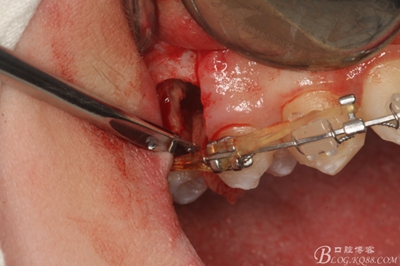

圖11.仔細考慮之后,在14頰側做垂直切口,切口長度僅達膜齦聯(lián)合處,做小切口。

圖12. 做垂直切口+齦溝內(nèi)切口,形成角形瓣,暴露出15根面。